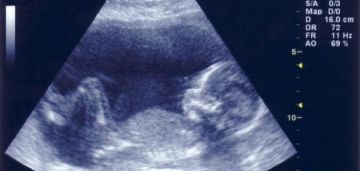

طرق معرفة جنس الجنين في الشهر السابع